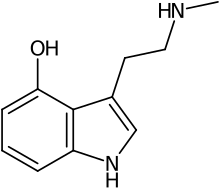

| Nω-Methylserotonin (norbufotenin) | Plants | 5-OH | H | CH3 | 5-hydroxy-N-methyltryptamine | 1134-01-6 |